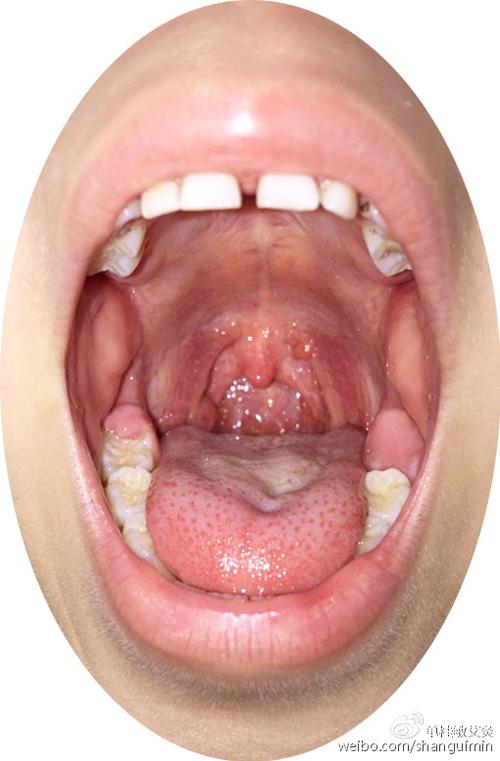

急性咽炎图片

急性咽炎的症状

急性咽炎真实图片

急性咽炎口腔图片

急性咽炎的症状图片

急性咽炎图片高清图片